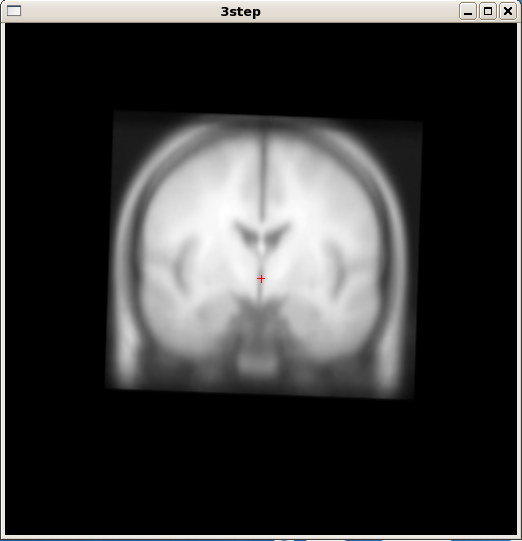

3step : 3手順で行う場合に使用するサブジェクト名。

3手順の順次実行

サブジェクト名(SUBJECTS) の設定など. ここでは,サブジェクト名を「3step」に設定

export SUBJECTS_DIR=/usr/local/freesurfer/subjects export SUBJECTS=3step cd $SUBJECTS_DIR mkdir $SUBJECTS cd $SUBJECTS mkdir mri cd mri mkdir orig cp ../../bert/mri/orig/001.mgz orig/ tkmedit $SUBJECTS ./orig/001.mgz &*FreeSurferの実行方法(3手順)

recon-all -autorecon1 -s 3step recon-all -autorecon2 -s 3step recon-all -autorecon3 -s 3step

「3手順」で行った場合

手順1: 「recon-all -autorecon1 -s 3step」の出力結果の確認. 頭蓋骨除去後の頭部ボリューム画像データ

tkmedit 3step brainmask.mgz

手順2: 「recon-all -autorecon2 -s 3step」の出力結果の確認 (1) 脳膜のボリューム画像データ

tksurfer 3step lh pial

手順2: 「recon-all -autorecon2 -s 3step」の出力結果の確認 (2) 白質のボリューム画像データ

tksurfer 3step lh white

手順2: 「recon-all -autorecon2 -s 3step」の出力結果の確認 (3) 膨張脳膜のボリューム画像データ

tksurfer 3step lh inflated -gray lh.curv

手順3: 「recon-all -autorecon3 -s 3step」の出力結果の確認

tksurfer 3step lh sphere -gray lh.curv